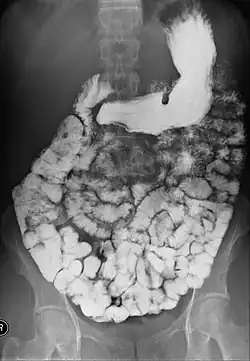

Small bowel follow-through

Indications to do this procedure are: unexplained chronic abdominal pain with weight loss, unexplained diarrhea, anemia which is caused by gastrointestinal bleeding or dependent on blood transfusion where the cause cannot be explained despite OGDS or colonoscopy investigations, partial obstruction of bowel/small bowel adhesive obstruction suspected, and unexplained malabsorption of nutrients.[13] For barium follow-through examinations, a 6-hour period of fasting is observed prior to the study.[10]

Barium is administered orally, sometimes mixed with diatrizoic acid (gastrografin) to reduce transit time in the bowel. Intravenous metoclopramide is sometimes also added to the mixture to enhance gastric emptying.[17] 600 ml of 0.5% methylcellulose can be given orally, after barium meal is given, to improve the images of small bowel follow-through by reducing the time taken for barium to pass through the small intestines, and increase the transparency of the contrast-filled small bowels.[18] Other methods to reduce transit time are to add ice cold normal saline after the administration of barium saline mixture[19] or to give a dry meal.[20]

X-ray images are then taken in a supine position at intervals of 20–30 minutes. Real-time fluoroscopy is used to assess bowel motility. The radiologist may press or palpate the abdomen during images to separate intestinal loops. The total time necessary for the test depends on the speed of bowel motility or transit time and may vary between 1 and 3 hours.[17]

- Barium follow-through examinations are the most commonly used imaging technique in assessing patients with Crohn's disease, although CT and magnetic resonance imaging are widely accepted as being superior.[1] However Barium examinations remain superior in the depiction of mucosal abnormalities.[24] The features of Crohn's disease are well described by barium follow-through examinations, appearing as a typical "cobblestone pattern", but no information is obtained regarding extraluminal disease.[28] Radiographic imaging in Crohn's disease provides clinicians with objective evaluations of small bowel regions that are not accessible to standard endoscopic techniques.[29] Because of its length and complex loops, the small intestine is the most difficult part of the gastrointestinal tract to evaluate. Most endoscopic techniques are limited to the examination of proximal or distal segments, hence Barium follow-through remains in most centres the test of choice for the investigation of abdominal pain, diarrhoea and in particular diseases manifesting mucosal abnormalities such as coeliac and Crohn's disease.[26]